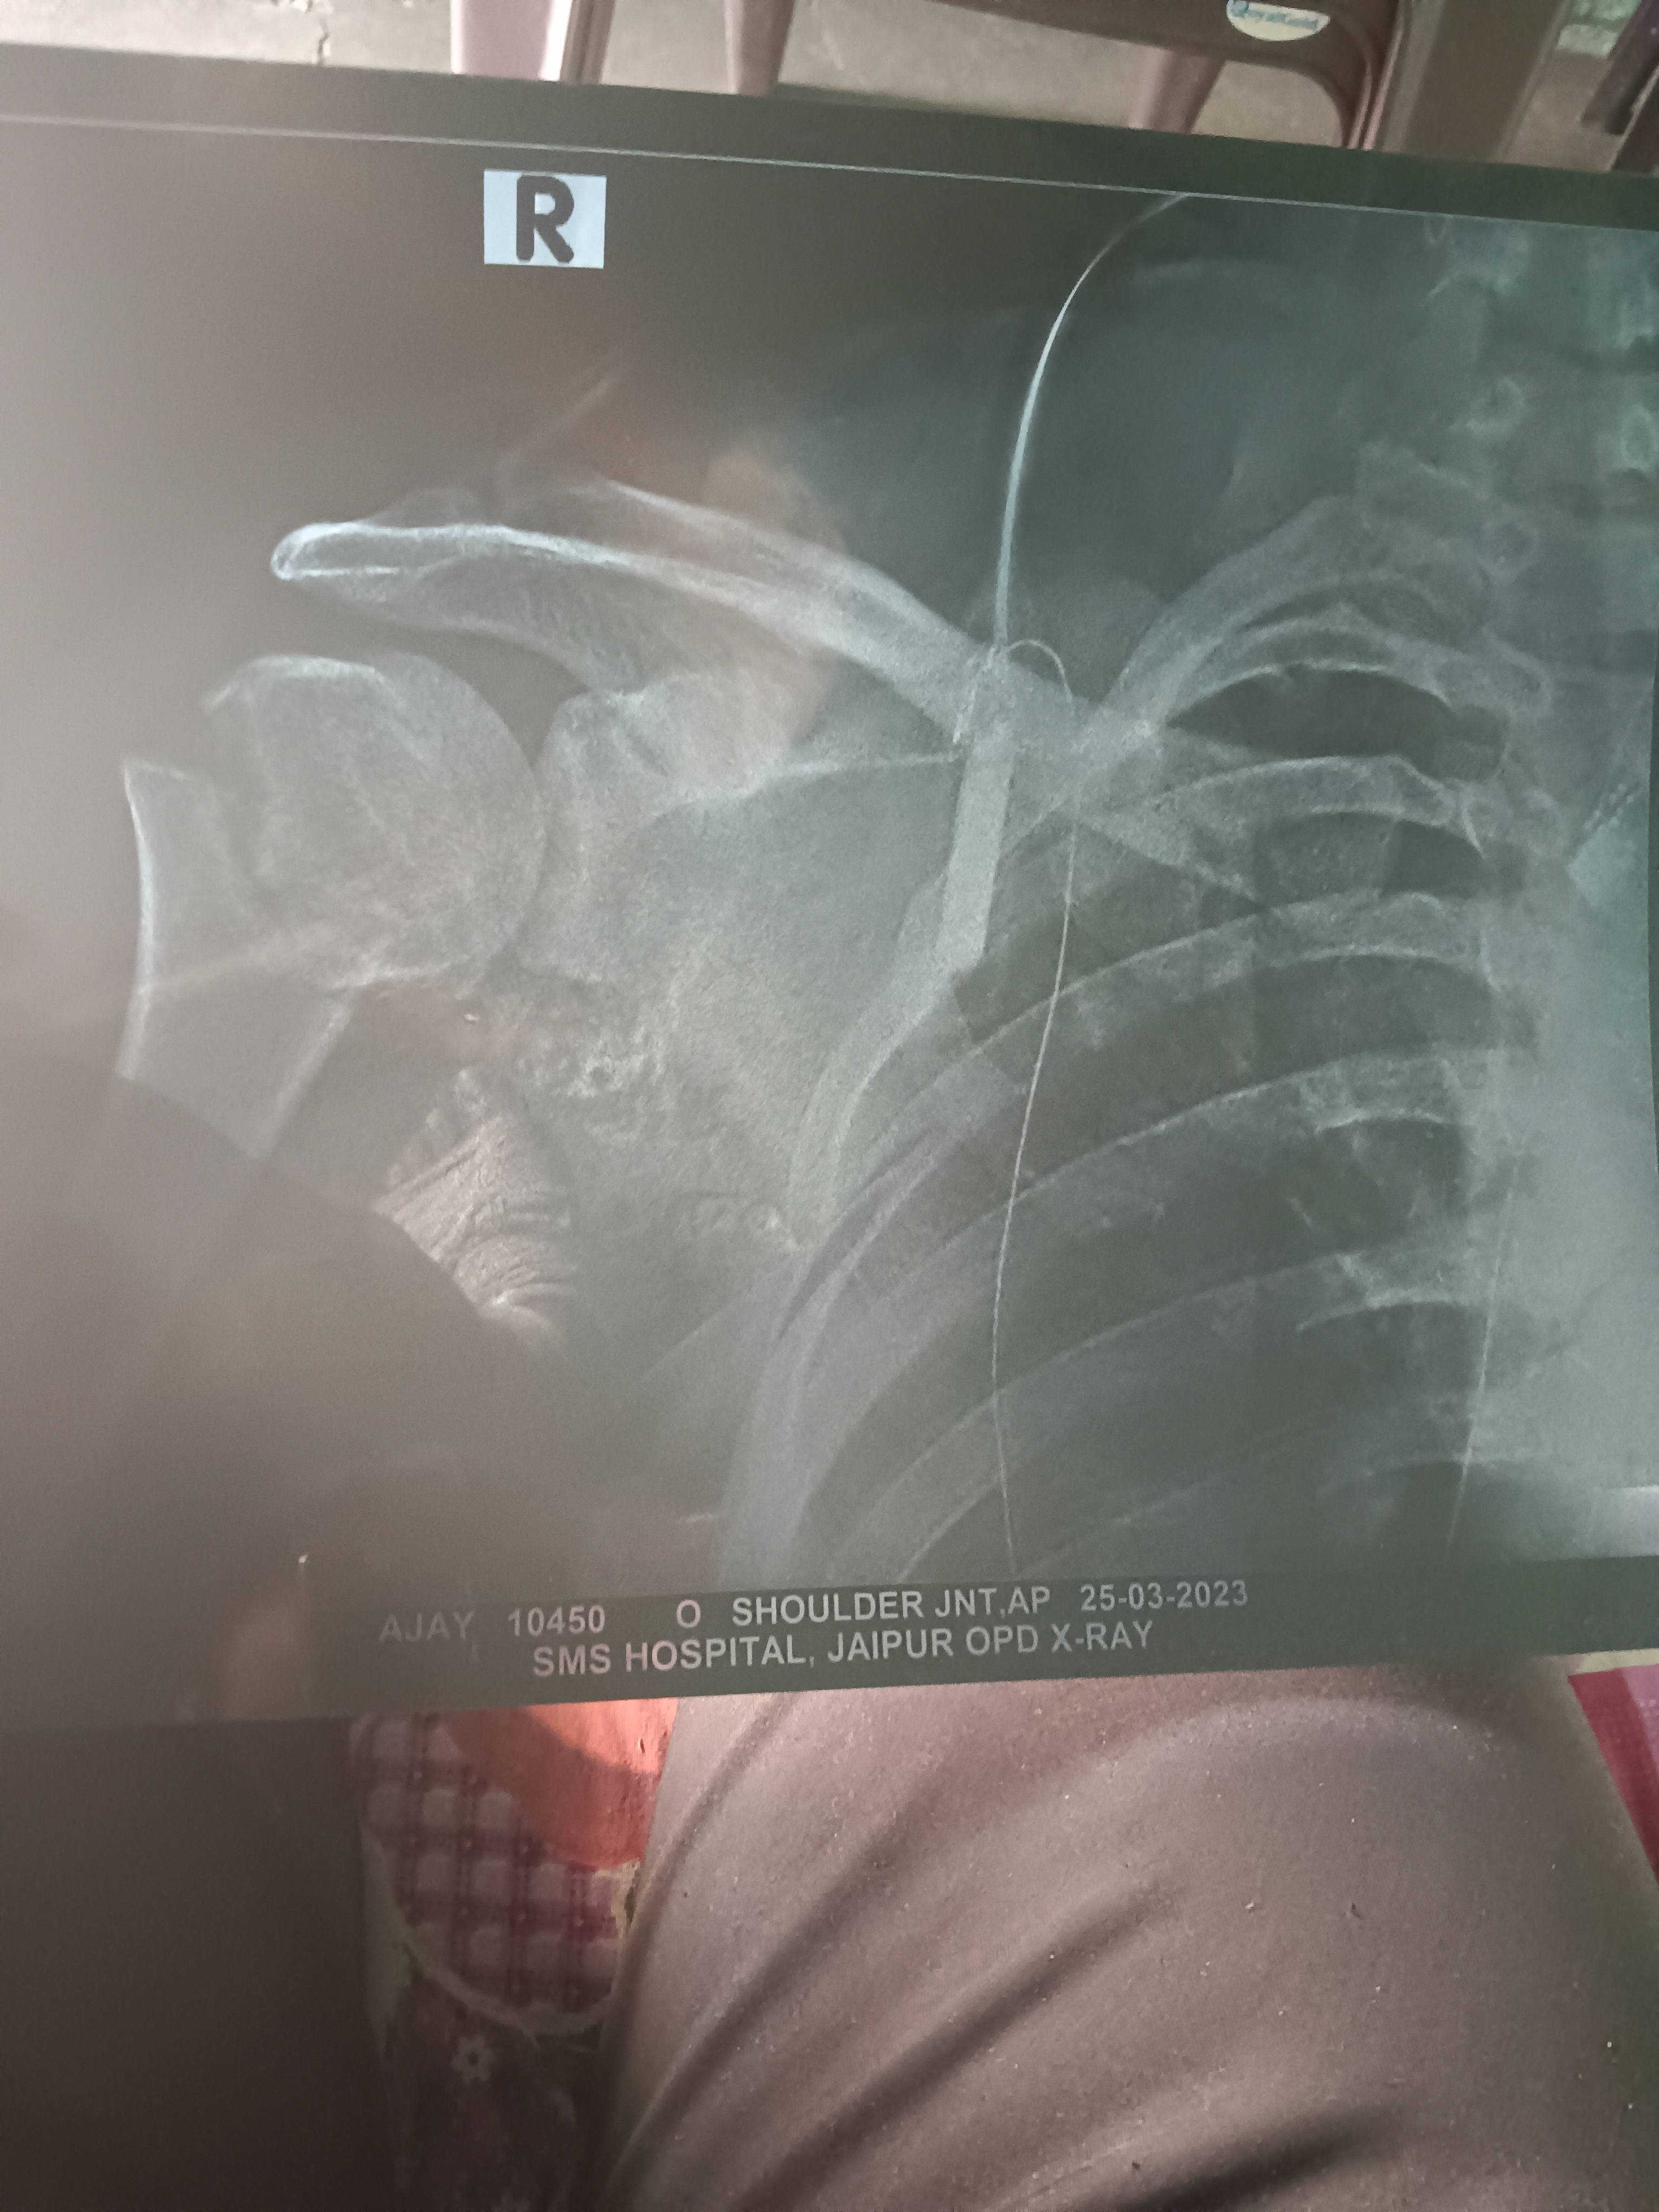

Sir right shoulder rotar cut injury

Sir this one is x ray on 7 month post surgery what should i do my doc suggest me to remove it after one year what's you suggestion